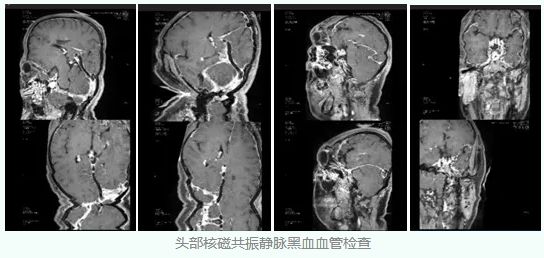

经过磁共振最新的黑血技术检查,刘女士的右侧横窦和乙状窦是发育变异,而左侧的乙状窦出现了严重狭窄,这就是造成刘女士颅内压力增高的根本原因。

至此,刘女士的真正病因终于浮出水面,刘女士先天的右侧横窦乙状窦发育变异,在此基础上左侧乙状窦出现了狭窄,造成脑静脉血回流受阻,导致颅内压增高,进而造成双侧视乳头水肿,从而造成双眼视力下降。

明确了病因之后,慕璐岩教授为患者制定了手术计划,先行全脑血管造影术同时进行静脉窦测压,如果狭窄造成静脉压力的明显差异,便进行支架置入来解决。

在完善了充分的术前准备后,慕璐岩教授和杨钊教授为患者实施了微创介入手术,全脑血管造影显示左侧乙状窦明显狭窄。